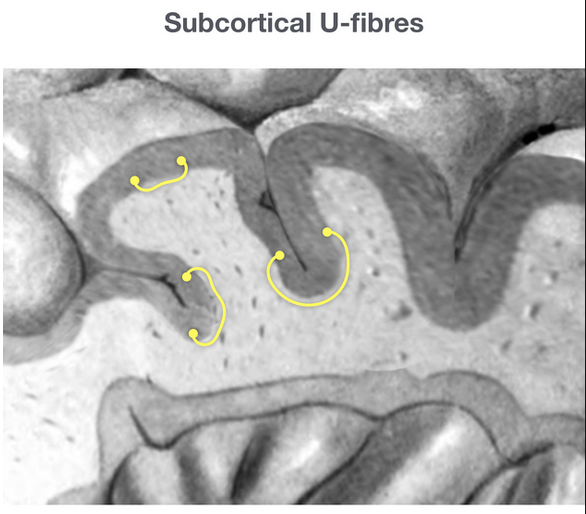

• Asymmetric, multi-focal, bilateral lesions - really anywhere but key place is subcortical U fibers

• Case courtesy of Frank Gaillard, Radiopaedia.org, rID: 58883 (subcortical U fibers)